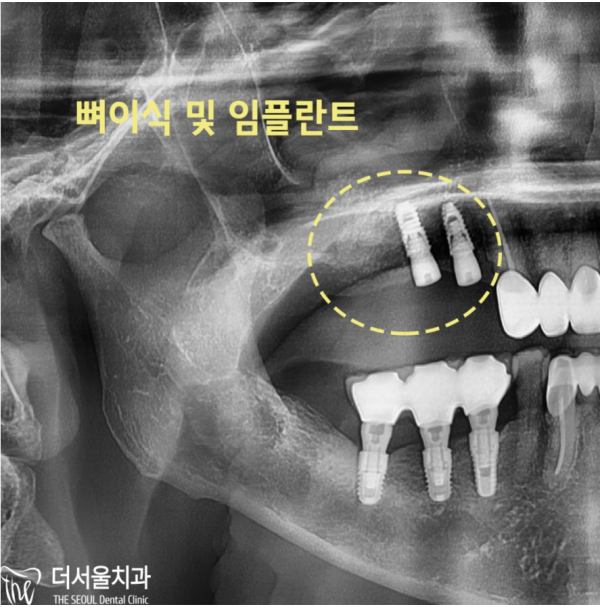

네비게이션 임플란트 진단을 통해 상악동에 있는 염증을 확인하고

골질까지 확인할 수 있었습니다. 뼈가 얇아져 있어 임플란트를 심기 어려워

상악동 거상술 후 뼈이식을 하기로 하였습니다.

Check the inflammation in the maxillary sinus through the diagnosis of the navigation implant

I was able to check the bone quality. It's hard to plant implants because the bones are thin

We decided to do a bone transplant after the maxillary sinus colostomy.

모란역치과 더서울치과의 네비게이션 임플란트 진단 결과에 따라서

임플란트 수술과 뼈이식을 하게되었습니다.

According to the results of the diagnosis of the navigation implant of Moran Station Dental Clinic The Seoul Dental Clinic

I got an implant surgery and a bone transplant.